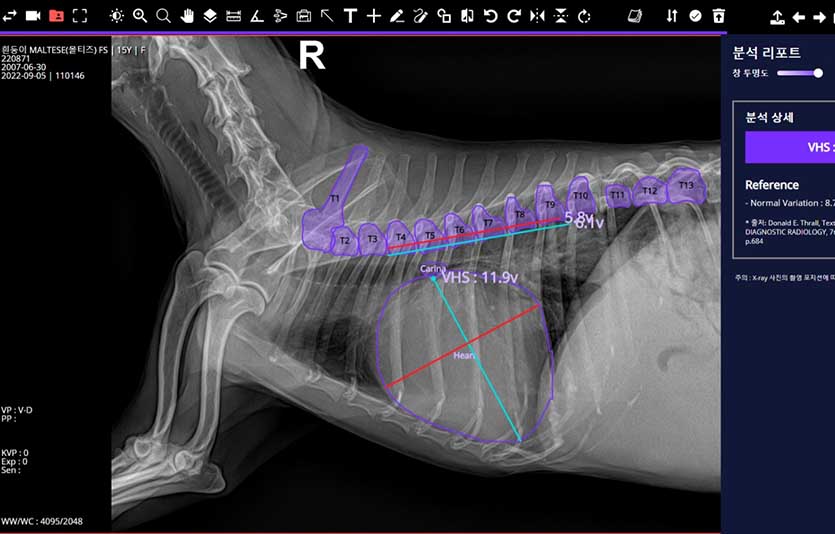

‘엑스칼리버는 병원에서 촬영한 반려견의 근골격(근골격계 질환 7종) 및 흉부(흉부 질환 10종) 등 엑스레이 사진을 클라우드에 올리면, AI가 약 30초 내(인터넷속도 100Mbps 기준) 비정상 소견 여부와 위치정보 등 분석결과를 수의사에게 제공하는 웹기반 서비스다. 이때 수의사는 엑스칼리버는 AI플랫폼 ‘엑스칼리버 VET AI’에 엑스레이 사진을 올리면 된다.

SK텔레콤에 따르면 엑스칼리버는 AI의 판독 결과와 국내 대형 동물병원 영상전공 수의사들의 판독 결과를 비교해본 결과, 양측 의견이 합치하는 비율이 분야별로 84~97%로 나타났다.

세부적으로는 ▲반려견 근골격 이상 영역 7종 검출모델 평균 질환탐지율(민감도) 86% ▲반려견 흉부 이상 패턴 10종 분류모델 평균 질환탐지률 84% ▲반려견 VHS(심장크기측정) 측정모델 정확도 97%를 기록했다.

질환 탐지율(민감도)은 반려견 질환에 대한 AI의 엑스레이 판독과 수의사의 판독 결과와 합치하는 정도를 표현하는 말이다. 정확도는 VHS 수치에 대한 정확도를 의미한다. 엑스칼리버는 이달 중순 농림축산검역본부로부터 ‘국내 제1호’ 엑스레이 기반 동물의료영상 검출 보조 소프트웨어 허가를 획득했다.